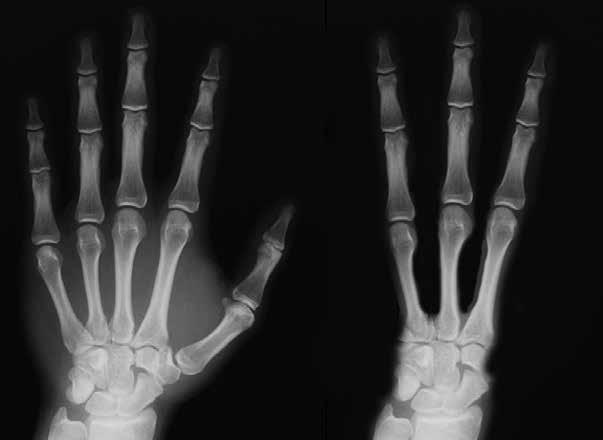

Ten pohled vyrážel dech. Hned za vchodem do nízké jeskyně seděla podivná mumie. Vysušené tělo bylo nezvykle bílé, jako by ho kdosi celé přetřel sádrou a nevynechal ani pootevřená ústa. Protáhlé hlavě dominovaly nepřirozeně velké vypouklé oči. Ruce i nohy ukončovaly pouze tři nelidsky dlouhé prsty.

Představitelé vědy mohli tedy do boje vytáhnout jen proti tomu, co sice viděli na vlastní oči, ale zprostředkovaně přes monitor počítače. Biolog Rodolfo Salas-Gismondi z univerzity v Limě vystoupil s domněnkou, že velký tříprstý mimozemšťan byl vyroben ze skutečné předkolumbovské mumie. Šlo o člověka, jemuž byla již v kojeneckém věku uměle deformována

lebka do prodlouženého tvaru, jak to v Peru praktikovaly mnohé staré civilizace. Soudobí plagiátoři mu ovšem z každé končetiny usekli palec a malíček a jejich články použili k prodloužení zbývajících tří prstů. Tak vznikl dojem působivých „mimozemských“ pařátů. Stopy po tomto zásahu měl zakrýt nános sádry. Malí vetřelci pak byli vyrobeni skládáním různých částí lidských a zvířecích těl. z hlav jim přitom byly odříznuty nos a uši.

Až na tři prsty na končetinách se tato mumie na prvý pohled neliší od člověka. Dokonce i poloha vsedě s koleny přitaženými k tělu je pro Peru typická.